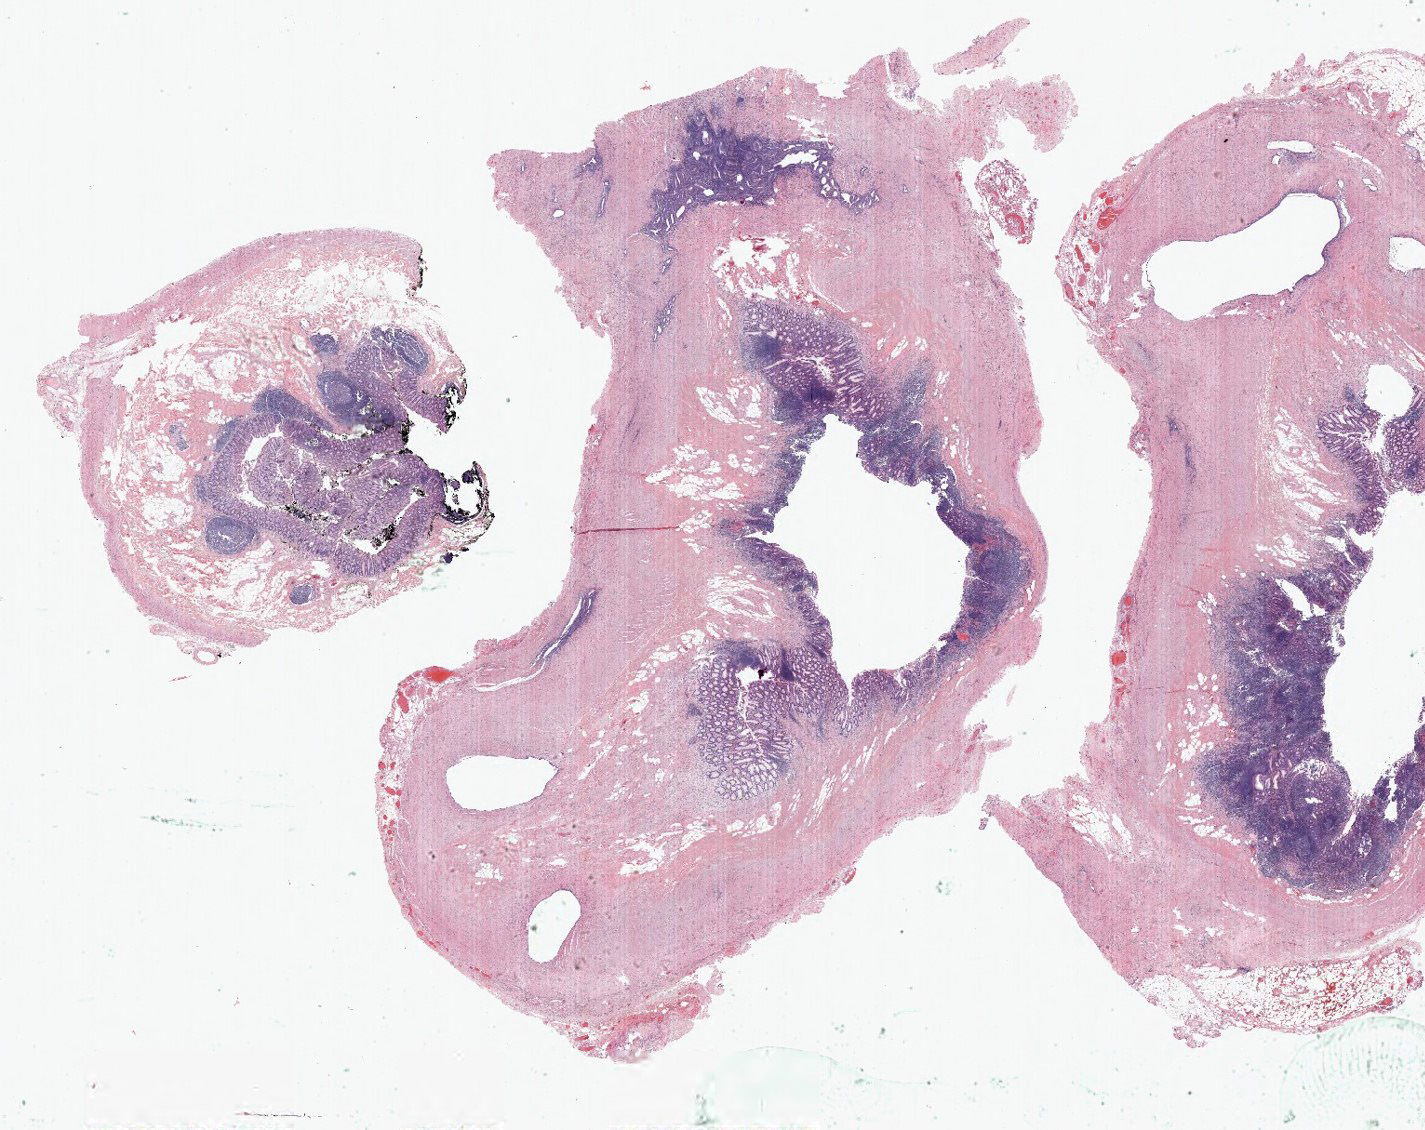

- Appendiceal endometriosis:

- Typically has a nonspecific presentation; pain may wax and wane with the menstrual cycle

- Most often affects the serosa or muscularis propria and is accompanied by abundant fibrosis and adhesions

- Microscopically, consists of endometrial type glands and stroma associated hemosiderin deposition and a fibroblastic response (Afr Health Sci 2008;8:196)

- Appendiceal diverticulosis:

- Congenital (true) or acquired (false) (incidence 0.014% and 1.9%, respectively) (Hum Pathol 2008;39:1823)

- Occurs in relatively older age group (Surg Today 2012;42:363)

- Symptoms mimic acute appendicitis; higher risk of perforation than acute appendicitis (Surg Today 2012;42:363)

- Often associated with higher risk of neoplasm, especially neuroendocrine tumor and mucinous neoplasms (Int J Surg Case Rep 2017;33:31)

A 35 year old woman presented with localized right lower quadrant abdominal pain for 1 day. She also presented with nausea, vomiting, menorrhagia and dizziness. She reported that she was actively menstruating and that these symptoms typically occurred monthly with menstruation but had been particularly severe in that month. CT scan showed thick walled appendix consistent with acute appendicitis. She underwent an appendectomy. The H&E images are shown above. Which of the following is the most likely diagnosis?

- Appendiceal endometriosis